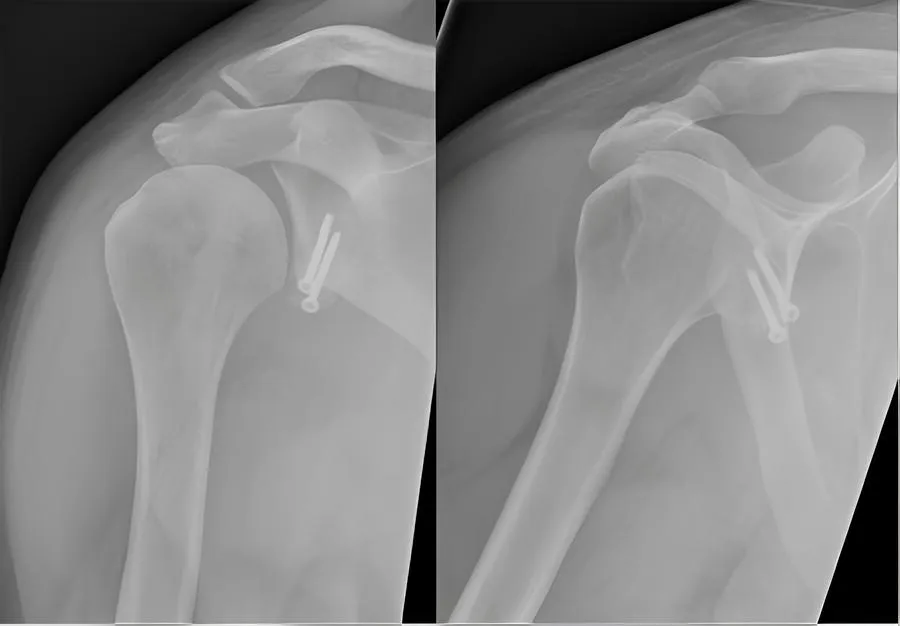

Recurrent Shoulder Dislocation

Bankart Lesion

Rotator Cuff Tear